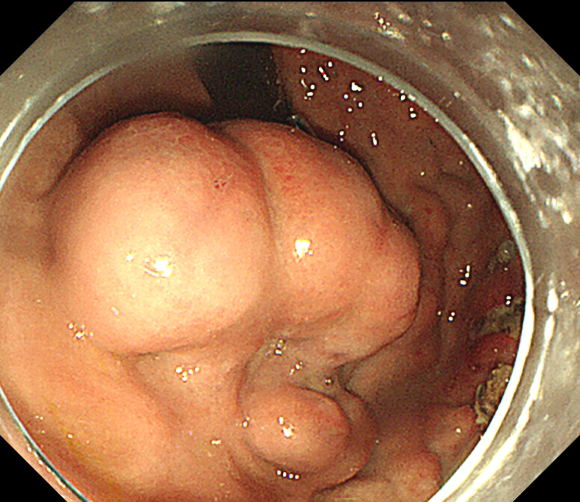

孤立性胃底巨大曲张静脉

接受手术的患者因急性消化道大出血,被送至北京清华长庚医院急诊科,反复发作的大出血伴随着失血性休克像一颗“定时炸弹”时刻威胁着患者的生命。胃镜检查的结果显示出血是由孤立性胃底巨大曲张静脉引起,此时此刻,只有封堵曲张静脉才有可能从根本上解决问题。

食管胃底静脉曲张非常凶险,是肝硬化失代偿期门脉高压最常见且最严重的并发症之一,也是上消化道出血的常见病因。一旦发生破裂出血可致失血性休克,危及生命,首次病死率甚至高达33%。